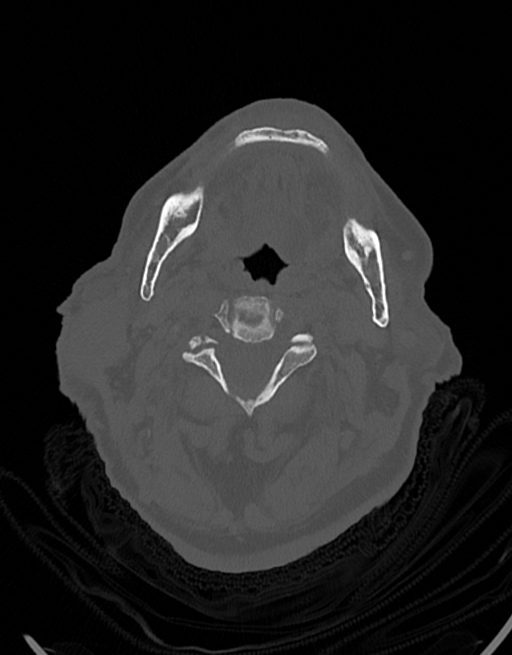

در سي تي اسکن اسپيرال نازو فارنکس با و بدون کنتراست (مولتي ديدکتور 16 با مقاطع ظريف و بازسازي هاي ساژيتال و کرونال):

– توده نسج نرمي به ابعاد mm 40 x 45 x 60 در ناحيه پاروتيد راست، با enhancement هتروژن پس از تزريق کنتراست مشهود است که مطرح کننده آدنوم پاروتيد مي باشد.

– شواهدي از تهاجم توده به استخوان و عروق اطراف مشهود نيست .

– کلسيفيکاسيون در ديواره شريان هاي کاروتيد دو طرف مشهود است .

– بررسي بافتي توده پاروتيد راست پيشنهاد مي شود .